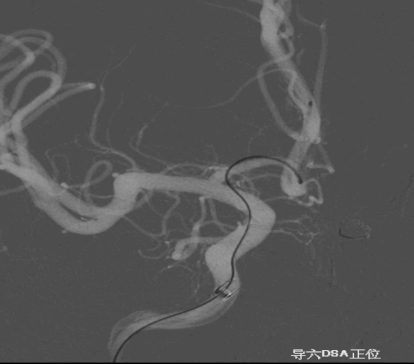

术前外院 DSA 2025-02

箭头所指右侧A1微小动脉瘤

6F Envoy DA在泥鳅导丝辅助下超选至右侧颈内动脉海绵窦段后膝。

工作位正位造影(图片)